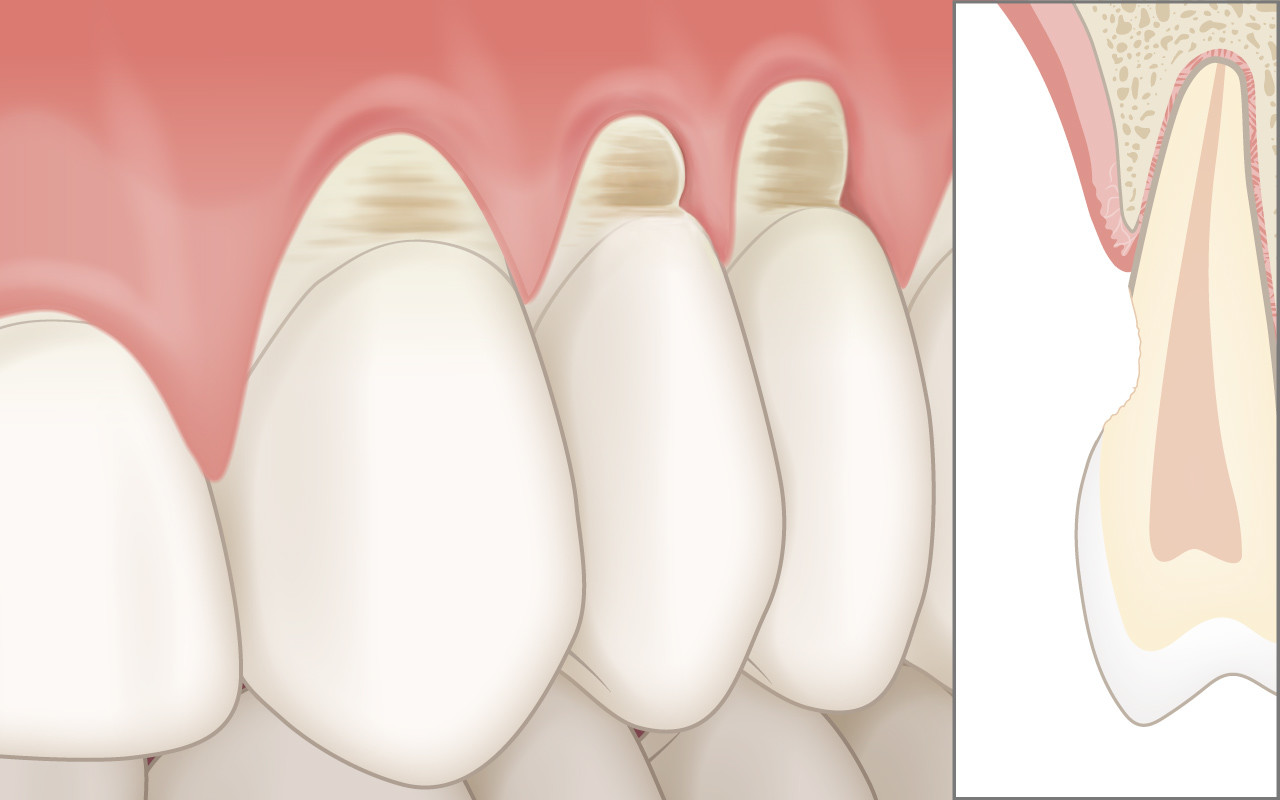

Abgetragene Zahnhälse (Abrasionen)

Die Hartsubstanzen der Zahnwurzel (Zement und Dentin) sind weicher als die Substanz der Zahnkronen (Schmelz). Deshalb können am Zahnfleischrand sogenannte abgetragene Zahnhälse (Abrasionen) entstehen.

Die geringere Härte der Zahnsubstanz an der Oberfläche der entblössten Zahnwurzel wird bei anhaltender falschen Mundhygiene-Technik zur Abtragung (Abrasion) der Wurzeloberfläche führen. Dadurch werden Eindellungen gebildet, die aufgrund ihrer Form auch als keilförmige Defekte bezeichnet werden.

Bei einer fehlenden Anpassung der Zahnputz-Technik, können bei jeder neuen Wischbewegung die Borstenenden einer Zahnbürste erneut grosse Kräfte auf das weichere Dentin ausüben. Dadurch wird der Vorgang der Abrasionsbildung weiter verstärkt.

Bereits fortgeschrittene Abrasionen mit einer Tiefe von mehr als einem Millimeter können mit einer Kunststofffüllung versorgt werden. Diese Behandlung führt in der Regel sofort zur Verminderung der Zahnhalsüberempfindlichkeit.